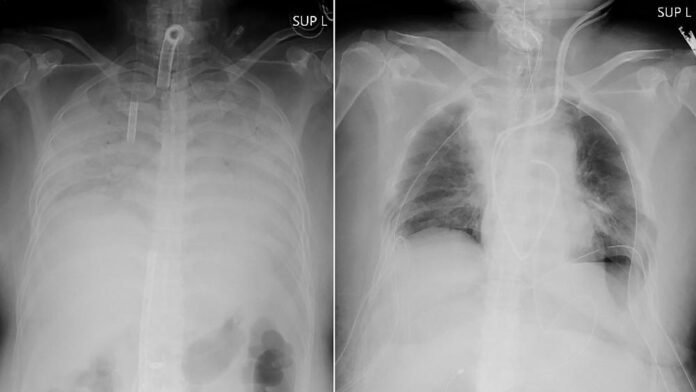

Doctors in Japan announced Thursday they have successfully performed the world’s first transplant of lung tissue from living donors to a patient with severe lung damage from COVID-19.

The recipient, identified only as a woman from Japan’s western region of Kansai, is recovering after the nearly 11-hour operation on Wednesday, Kyoto University Hospital said in a statement. It said her husband and son, who donated parts of their lungs, are also in stable condition.

“We demonstrated that we now have an option of lung transplants (from living donors),” Dr. Hiroshi Date, a thoracic surgeon at the hospital who led the operation, said at a news conference. “I think this is a treatment that gives hope for patients” with severe lung damage from COVID-19, he said.

Her husband and son volunteered to donate parts of their lungs, and the surgery was conducted at Kyoto University Hospital by a 30-member team headed by Dr. Date. Her husband donated part of his left lung, and son gave part of his right lung.

She is expected to be able to leave the hospital in about two months and return to her normal life in about three months, the university said.